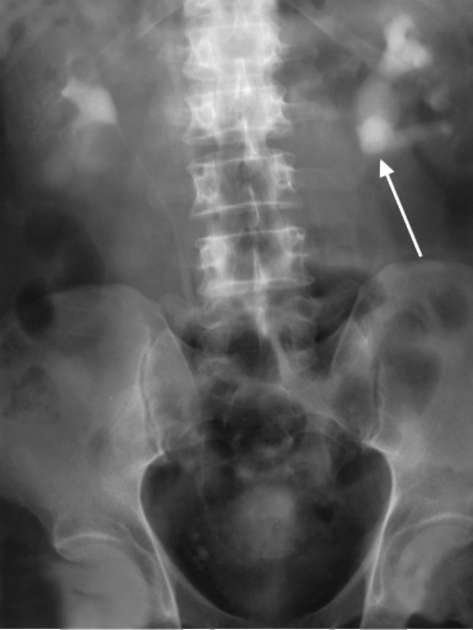

Обзорная урография позволяет определить рентгеноконтрастные свойства камней, что помогает предположить их состав, а также установить их размеры и расположение.